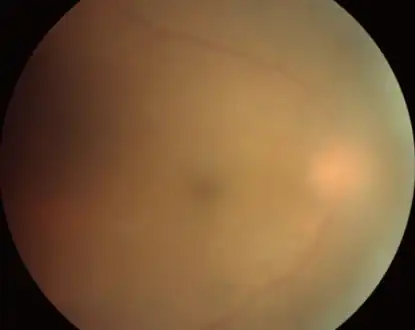

Acute toxoplasmosis is often asymptomatic in healthy adults.[13][14] However, symptoms may manifest and are often influenza-like: swollen lymph nodes, headaches, fever, and fatigue,[15] or muscle aches and pains that last for a month or more. It is rare for a human with a fully functioning immune system to develop severe symptoms following infection. People with weakened immune systems are likely to experience headache, confusion, poor coordination, seizures, lung problems that may resemble tuberculosis or Pneumocystis jiroveci pneumonia (a common opportunistic infection that occurs in people with AIDS), or blurred vision caused by severe inflammation of the retina (ocular toxoplasmosis).[15] Young children and immunocompromised people, such as those with HIV/AIDS, those taking certain types of chemotherapy, or those who have recently received an organ transplant, may develop severe toxoplasmosis. This can cause damage to the brain (encephalitis) or the eyes (necrotizing retinochoroiditis).[16] Infants infected via placental transmission may be born with either of these problems, or with nasal malformations, although these complications are rare in newborns. The toxoplasmic trophozoites causing acute toxoplasmosis are referred to as tachyzoites, and are typically found in bodily fluids.[17][18]

-

Fundus image of choroidal neovascularization in ocular toxoplasmosis -

Infection of the vitreous body in toxoplasmosis of the eye